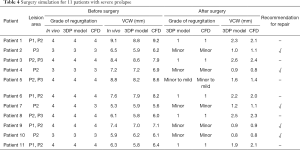

There were 21 patients who were transferred to mitral replacement. Of them, 11 had a severely prolapsed PML and excessive removal contributed to adverse outcomes after surgery and even a second operation. We simulated the MV repair procedure in these patients using the 3DP model and CFD, and found that 5 of them tolerated surgery well with only minor MR. The other 6 patients had mild or more MR after surgery. Details of the patients before and after surgery are summarized in Table 4.

Full table

Of the 21 patients who were transferred to mitral replacement, there was one with Barlow disease (BD). The MV leaflets were redundant, with prolapse of P2 and P3. 3D-TEE showed billowing of both AML and PML, especially the P3 segment. Color Doppler showed severe MR originating from the PML. One challenge of repairing BD mitral valves is the development of postoperative SAM of the AML, which is often associated with a tall PML. As the height of the PML increases, the coaptation point gets closer to the base of the AML, and the length of the AML beyond the coaptation point (residual length) increases. Residual AML is free to move in response to the drag created by the jet flow, which can cause SAM and LVOT obstruction. We simulated the procedure with different PML lengths from 14.0 to 19.0 mm (with an 0.5 mm increase on each attempt). The residual length of the AML ranged from 2.8 to 5.4 mm (Table 5). The results show that SAM and LVOT obstruction occurred when the PML length reached 16.5 mm, with a residual length of the AML at 4.2 mm (Figure 8). The pressure gradient at the LVOT reached 17.2 mmHg after repair, but was only 6.8 mmHg before surgery.

Full table